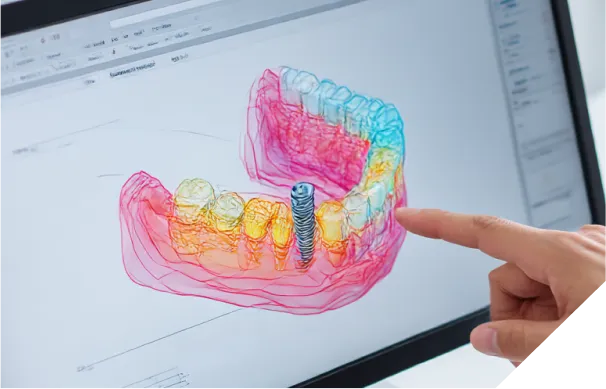

当院では、歯科用CTによる3D精密診断を必ず行います。骨の厚みや高さはもちろん、神経や血管の位置をミリ単位で正確に把握します。さらに、そのデータをもとにコンピューター上で手術のシミュレーションを行い、安全な位置・角度・深さを決定し、治療計画を立案します。また、これに基づいて ガイドテンプレートを作製し、偶発的な事故のリスクを限りなくゼロに近づけます。